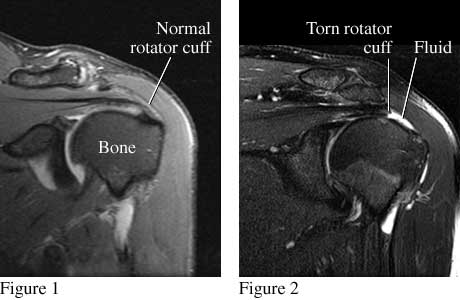

Figure 1 is a front view of the shoulder that shows a normal rotator cuff. Figure 2 is a similar view that shows a torn rotator cuff.